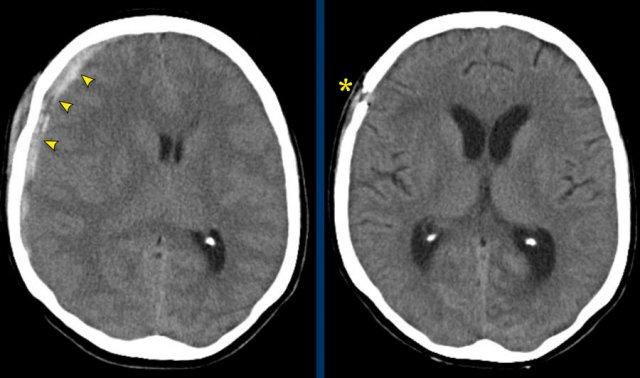

Bệnh nhân này có tụ máu dưới màng cứng cấp tính.

Có sự dịch chuyển đường giữa (hình bên trái).

Bệnh nhân đã được phẫu thuật và khối tụ máu được dẫn lưu (hình bên phải).

Các hình ảnh cho thấy tụ máu dưới màng cứng.

Lưu ý rằng khối tụ máu có cả vùng tăng tỷ trọng và đồng tỷ trọng.

Hình ảnh này có thể gặp trong chảy máu siêu cấp tính, nhưng cũng có thể gặp trong trường hợp chảy máu tái phát.

Có sự dịch chuyển các cấu trúc đường giữa kèm tắc nghẽn lưu thông dịch não tủy, dẫn đến giãn sừng thái dương của não thất bên phải (mũi tên).

Tụ máu dưới màng cứng cấp tính có tỷ trọng cao (máu đã đông), tụ máu bán cấp có đồng tỷ trọng, và tụ máu dưới màng cứng mạn tính có giảm tỷ trọng so với nhu mô não (đồng tỷ trọng với dịch não tủy).